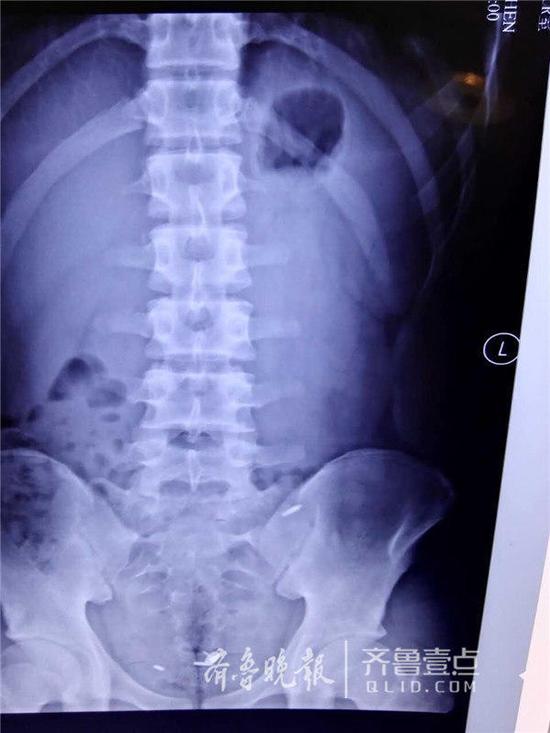

腹中的圆珠笔芯

因与同学打赌,济南一名16岁的少年竟口吞一枚图钉,并将三个圆珠笔芯头从肚脐生生塞入腹腔中。事发后,少年被送至山东大学齐鲁医院急救。医生们经过4个小时的艰难寻找,才通过腹腔镜将三个圆珠笔芯头取出,而那枚图钉也在第二天被幸运地排出体外,整个过程十分惊险。

“非常难找。”李鹏宇说,王川年龄还小,为了减少创伤,他们在王川的肚脐和左右腹部各打了一个小孔,然后通过腹腔镜进行探查,但没想到在艰难地找到一个圆珠笔芯头后就再也找不到了。“由于翻找,笔芯头一直在换地方,一会在上面,一会在下面;肠子的大网膜、肠间隙非常多,情况复杂。”术中,一度医生们考虑或许只能通过创伤大的开腹手术将其取出,但考虑到孩子年龄,又坚持了下去。终于,历经了4个小时的艰难寻找,才终于把三个长1厘米左右的笔芯头给取了出来。